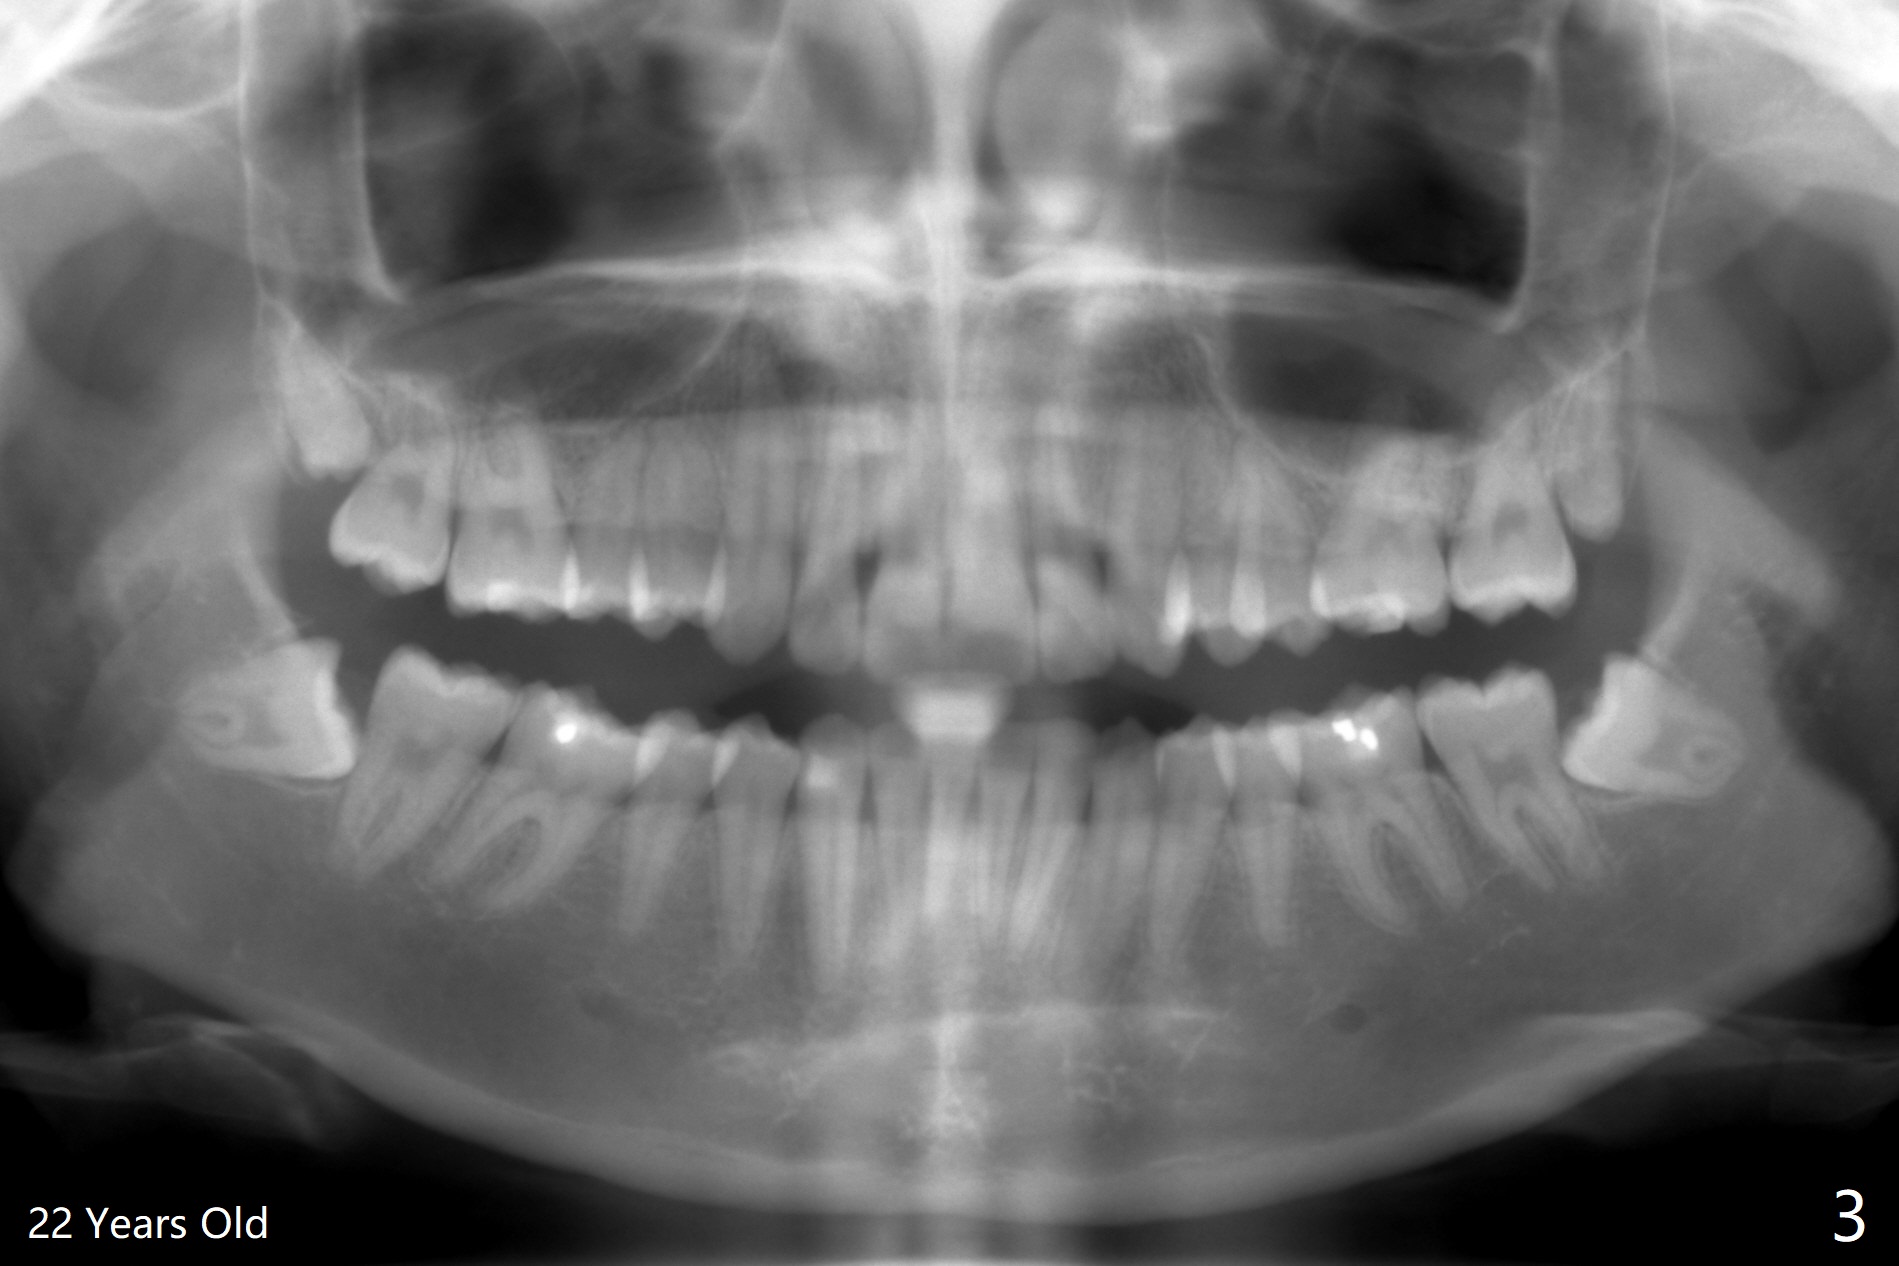

A 25-year-old woman, under our care for the last 11 years (Fig.1-6), returns for #1 and 32 extraction (1 year after #16 and 17 extraction (Osteogen plug)). Preop PA shows that a portion of the lower impacted tooth may be located buccal to the tooth #31 (Fig.4 black dashed line). An accessory incision is moved from distobuccal to midbuccal (Fig.7 arrowheads) to reduce postop loss of bone graft (Fig.8 B) from the incision. In fact the incision should be further moved to mesiobuccal (Fig.9 red line) if buccal impaction is suspected (curved black line). The buccal impaction of #32 of her father is more severe.